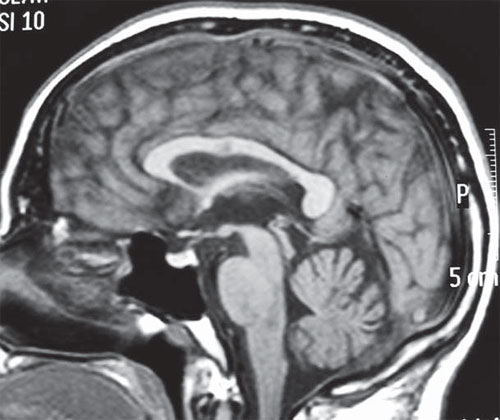

Fenitoína: los niveles séricos elevados pueden producir atrofia cerebelosa

02 agosto 2016